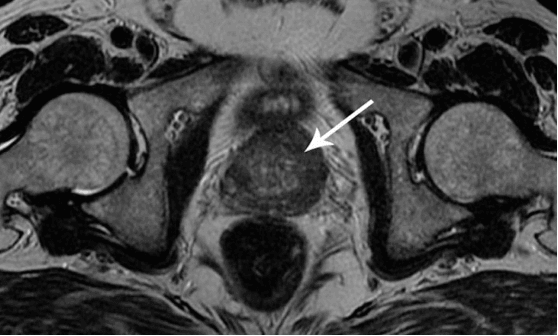

Ich möchte Ihnen ein paar Fotos zeigen, um zu zeigen, was im Urogenitalsystem und anderen Organen eines Mannes vor sich geht, der keinen Sex hat.

So sieht eine Entzündung der Prostata aus, die durch Stagnation der Spermien verursacht wird (wenn die Hoden nicht geleert werden). Eine anhaltende Entzündung führt zuerst zu einem Prostataadenom und dann zu Krebs. Dies ist eine unvermeidliche Folge von Prostatitis, daher wird es als "Krankheit der älteren Generation" bezeichnet.

Prostatakrebs bei einem Mann mit 58 Jahren.

Als Folge der Stagnation wird Cholesterin an den Wänden der Blutgefäße abgelagert, was zu einer Verengung ihres Lumens und zur Bildung von Mikrothromben führen kann. Dies beeinträchtigt die Versorgung der Prostata und unterstützt die Entzündung in ihr.